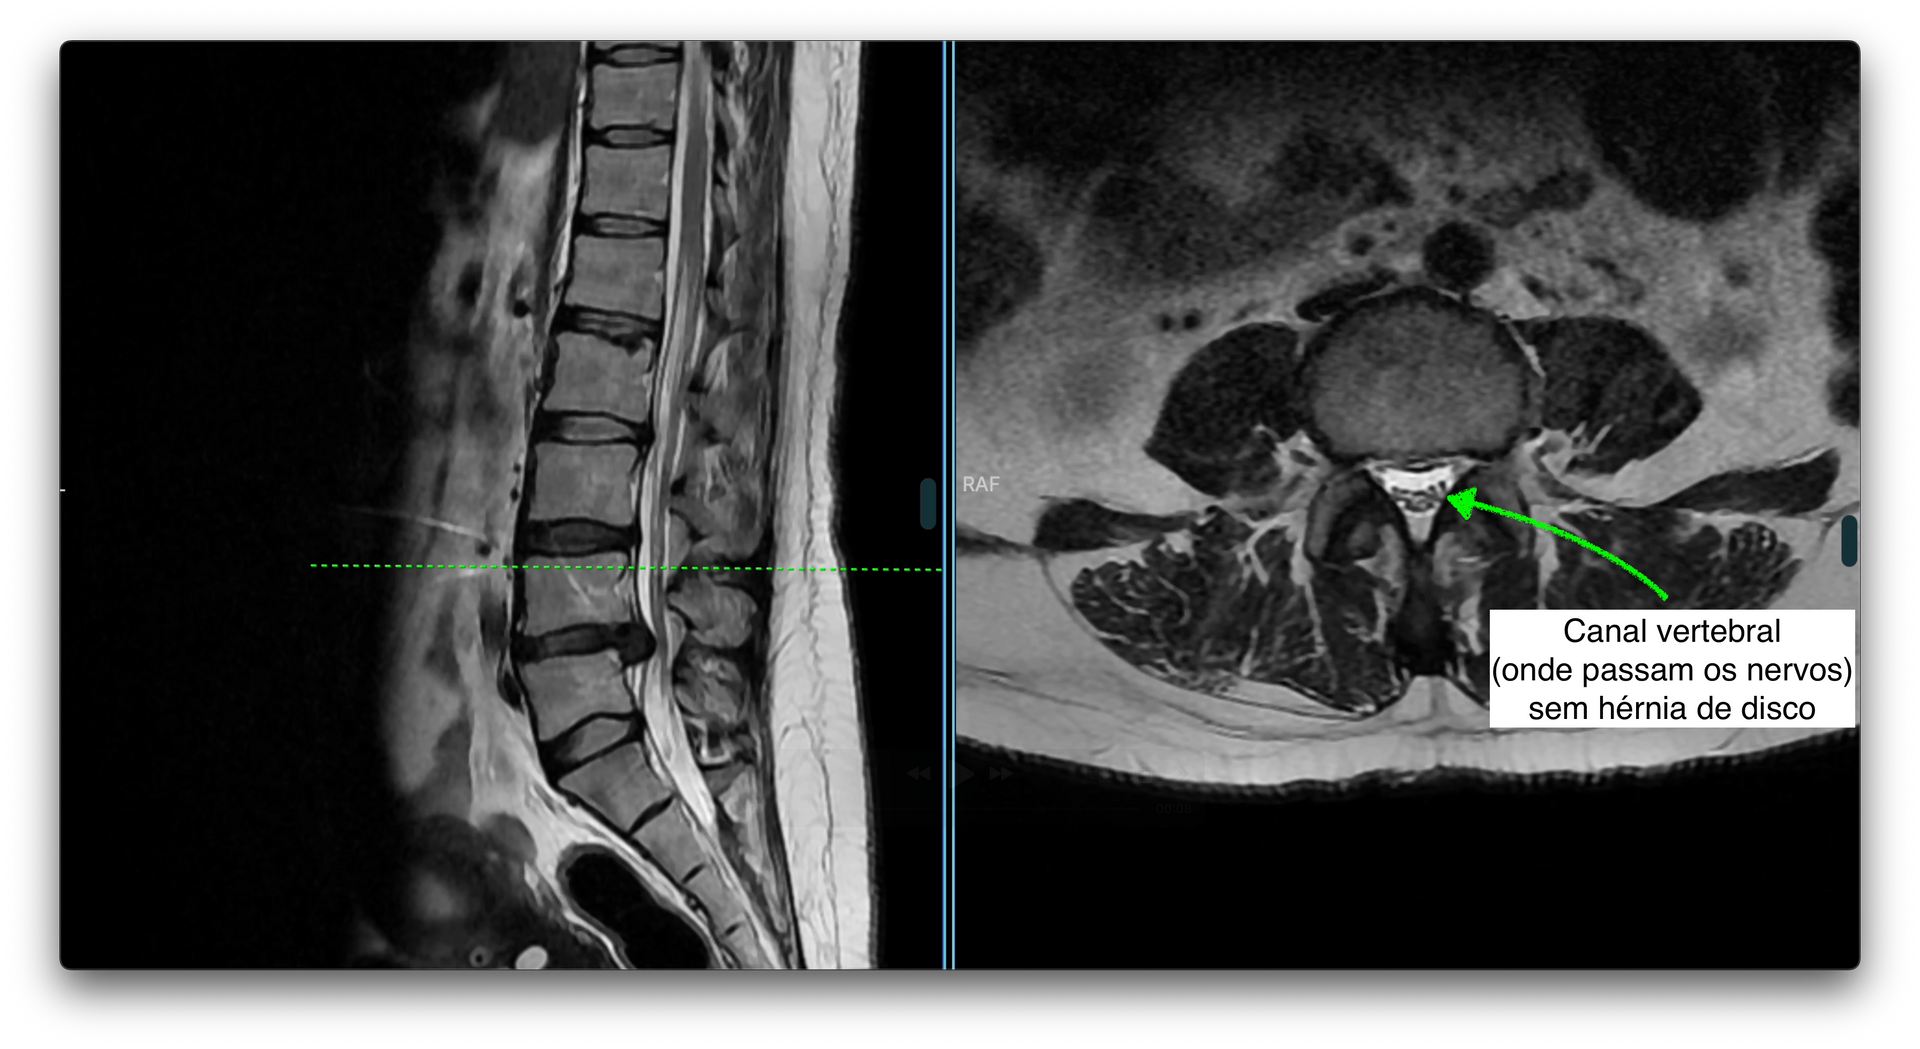

O principal exame de imagem é a ressonância magnética da coluna lombar, que mostra com detalhes a presença da hérnia, sua localização e se há compressão de raízes nervosas.

Entre as vértebras da coluna existe uma estrutura chamada disco intervertebral, que funciona como um amortecedor, permitindo mobilidade e absorvendo impactos. Esse disco é formado por um centro gelatinoso (núcleo pulposo) e uma parte mais resistente ao redor (ânulo fibroso).

Com o tempo, ou após sobrecargas repetitivas, o disco pode se desgastar e seu conteúdo interno pode se projetar para fora, formando o que chamamos de hérnia de disco. Quando isso acontece na região lombar (parte baixa das costas), chamamos de hérnia de disco lombar.

Essa hérnia pode comprimir estruturas nervosas próximas, como as raízes do nervo ciático, causando dor e outros sintomas.